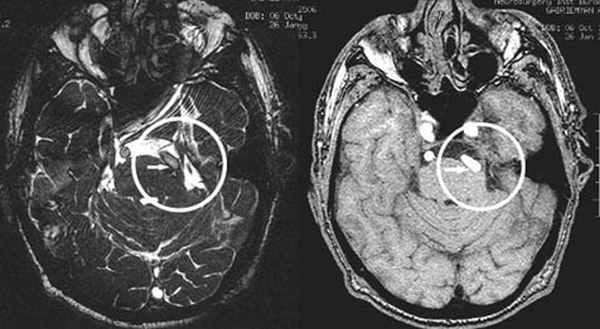

(Слева) При аксиальном исходном изображении (МРА) у пациента с спазмом правой половины лица визуализируются извитая правая позвоночная артерия и ЗНМА, воздействующие на область выхода корешка лицевого нерва. В цистерне мостомозжечкового угла (ММУ) визуализируется лицевой нерв.

(Справа) При аксиальной МРТ CISS на уровне цистерн ММУ у пациента с правосторонним гемифациальным спазмом определяется петля ЗНМА, смещающая ЧН VII в цистерне ММУ кзади, в результате чего он «свешивается» с заднего края слухового отверстия.

Аксиальный срез (А, Б), сагиттальная проекция (В). Определяется нейроваскулярный конфликт между артерией и тройничным нервом. Компрессия тройничного нерва прилежащей к нему артерией обозначена стрелкой.

У места выхода тройничного нерва из ствола головного мозга (обозначено кругом) определяется крупный артериальный сосуд, компремирующий указанный нерв. На противоположной стороне визуализируется корешок V нерва, на расстоянии от которого проходит аналогичный артериальный сосуд.